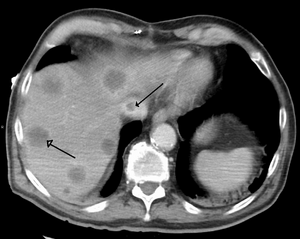

Budd–Chiari syndrome secondary to cancer; note clot in the inferior vena cava and the metastasis in the liver

Secondary Budd–Chiari syndrome, which is very rare compared to the primary variant, is due to compression of the hepatic vein by an outside structure (such as a tumor or polycystic kidney disease).[15]